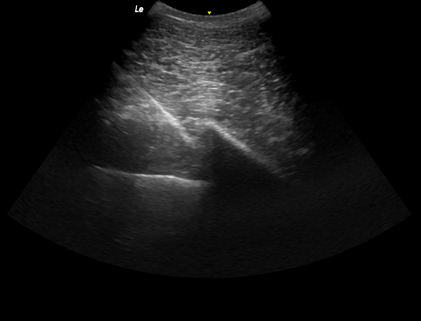

• Ultraschallgeführte Injektionen

Bei speziellen Befunden wie z.B. Facettengelenk-arthrosen im Brust-/Lendenwirbelsäulenbereich besteht die Möglichkeit, eine gezielte periartikuläre Injektion (mit z.B. Cortison / IRAP etc.) vorzunehmen. Die Ultraschallkontrolle unterstützt dabei eine sichere Applikation der Medikamente. Diese Technik wird auch bei anderen intraartikulären Injektionen im Oberlinienbereich zu Hilfe genommen, wie z.B. bei Facettengelenken der Halswirbelsäule oder beim Iliosakralgelenk (ISG).

Ultraschallgeführte ISG-Injektion